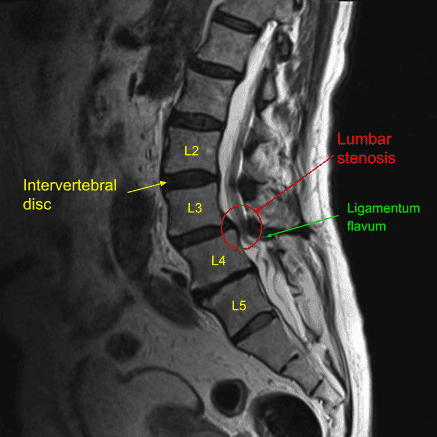

MRI of the lumbar spine in the sagittal section showing L4-L5 disc herniation.

The lumbar spine is made up of five vertebrae (L1-L5) separated by intervertebral discs. The discs serve as shock absorbers and allow movement between vertebrae. The spinal cord runs through the spinal canal and nerve roots exit through openings called foramina. These nerves control sensation and movement in the legs, and when compressed by a herniated or bulging disc, they can lead to pain, numbness, and weakness in the affected area.

- MRI (Magnetic Resonance Imaging): The best imaging technique for visualizing soft tissues, including herniated discs and nerve compression.

- CT Scan: Useful for detailed bone images, especially in the case of spinal stenosis.